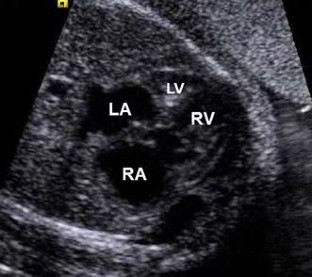

A Fetus With Hypoplastic Left Heart Syndrome and Tricuspid Stenosis With Evolving Hydrops Fetalis

Hypoplastic left heart syndrome (HLHS) is a severe congenital heart defect that results in death if not treated shortly after birth. In approximately 60 to 70% of cases, HLHS can be detected prenatally and generally is well tolerated due to the presence of the foramen ovale and ductus arteriosus, which allow for blood to bypass the left side of the heart but still provide adequate blood flow to the systemic circulation. A rare case of HLHS involving a fetus with tricuspid valve stenosis, abnormal venous Doppler findings, and hydrops is reported.